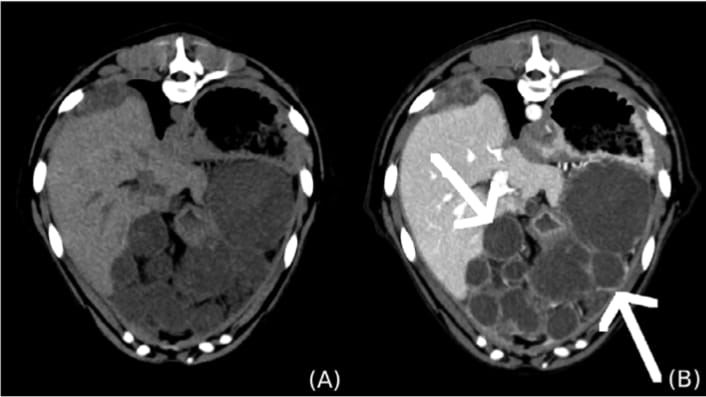

A), Pre- and (B) postcontrast transverse images showmultiple small, thin-walled, cavitary hepatic masses (white arrows) in adog diagnosed with hepatic alveolar echinococcosis. CT images werereconstructed with a soft tissue algorithm, matrix 512 × 512, slidethickness 2 mm, 120 kVp, 250 mA, 0.75 pitch.

Two primary lesion types were identified: large, thick-walled cavitary lesions with feathery wall mineralization and soft tissue septation (resembling AEUC IV), and smaller, thin-walled cystic lesions lacking mineralization. All lesions showed no central contrast uptake. The thick-walled lesions had minimal peripheral enhancement, while the thin-walled lesions showed marked wall enhancement. The liver lobes were variably involved, and some cases showed cystic lesions in other organs. Lymphadenopathy and reactive mesenteric fat were common. The findings support a hypothesis that smaller lesions may evolve into larger, mineralized forms.